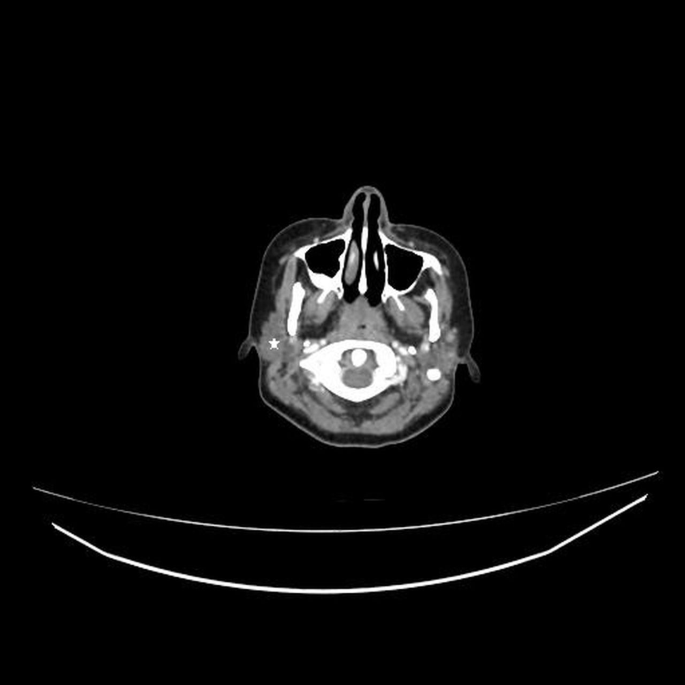

figure 5

Supplement Figure: Head and neck magnetic resonance imaging outline the enlargement of the right parotid gland (white star). (PNG 219 kb)